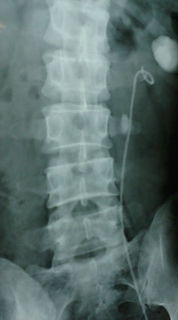

2008年06月03日(火) 「ステント入れましたよっ!」 日常

昨日とうとうステント入れたのでご報告。

レントゲン室に行ってくれっつーから行くと、何やらいつもと様子が違う。

いきなりステントかよと嘆きつつ、覚悟を決める。

服を脱いでスッポンポンになって、カモーン。

うつ伏せになってお尻の間の骨のところに2回、局部麻酔を打つ。

次は仰向けになって、ワシは妊婦さんかい?てな感じで足をオッピロゲ。

両足をそれぞれ左右の横の台にあげた状態で、ステントを注入していく。

チン○に入れられる際、激痛かと思いきや、麻酔が効いて特に痛みもない。

油断ならないので、大げさに痛そうにしておく。笑

羞恥心もどうでもよくなり淡々とステントが中に入っていく。

困ったのは膀胱に水を入れるときだな。

おしっこ漏れそうな感覚になるんだもんな、マジ漏れたらどうしようって思った。

総時間30分ぐらい、サクサクと作業を終え、レントゲン撮って終了。

ここまでして結局は開腹手術ですとかって、言わないでくださいよ。

次回は6月6日に、ステント入れての結石破砕の予定っす〜。

お約束の記念撮影

←この白い固まりは、造影剤の影

←ここからステント

←ここにあるのが結石

つーか背骨真っ直ぐにして写せよな(笑)

←このへんまでステント入ってますよん